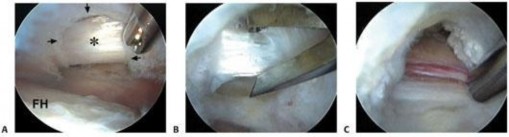

Central Compartment Transcapsular Release

The transcapsular release